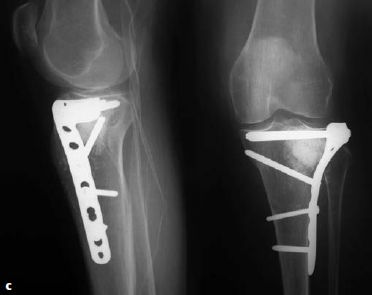

图6.8.1-17 a-n 一名62岁的男性车祸后左腿受伤(41A3.3)

a-b  X线显示左侧胫骨的节段性骨折。骨折近端有多条骨折线和一个楔形骨块,但是它们都没有移位或移位程度很小。整个骨折可以通过一根髓内钉进行固定,但是由于骨折位置非常高位,因此髓内钉手术将非常具有挑战性,因此最终选择采用MIPO技术进行钢板固定

c-d  关节面的骨折通过软骨下螺钉进行稳定固定,使用点式复位钳通过微创技术经皮复位近端的干骺端骨块,滑入胫骨近端锁定加压钢板,而后使用两枚克氏针在钢板两头进行临时固定

图6.8.1-17 a-n(接上图) 一名62岁的男性车祸后左腿受伤(41A3.3)

e-f  通过一枚单皮质复位螺钉将中间节段拉向钢板

g-h  在骨折区的内侧进行手法加压使得干部复位

i-j  当钻透坚硬的皮质时,干部会被推开,而后再次通过一枚单皮质复位螺钉将其复位

k-n  关节面的骨折通过软骨下螺钉进行稳定固定,使用点式复位钳通过微创技术经皮复位近端的干骺端骨块,滑入胫骨近端锁定加压钢板,而后使用两枚克氏针在钢板两头进行临时固定。

术后X线的力线可以接受。注意骨折的每个部分,工作长度都长达3个螺孔(双头箭头)。拉力螺钉打入近端骨折区来维持楔形骨块。但是一般来说,并不推荐在桥接区域放置拉力螺钉,因为它可能会妨碍跨骨折区的微动,从而妨碍骨折愈合。远端内侧的钢板位置稍微偏前以避免和外侧锁定板的螺钉钉道发生冲突。所有的骨折最终均平稳愈合